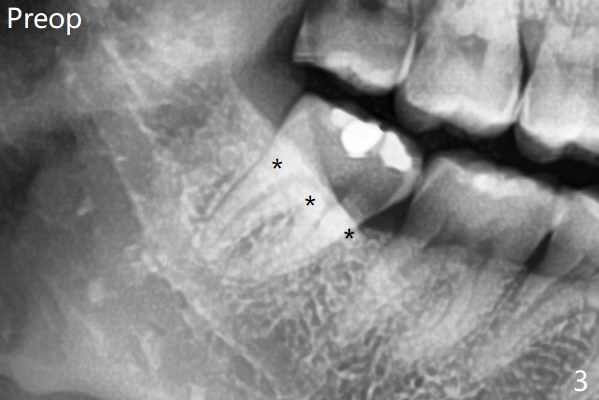

Since no buccal trough is made for extraction, the external oblique ridge (*) is present at #17 and 32 before and after surgery. Bond Apatite is placed with Collagen Plug (Fig.7).